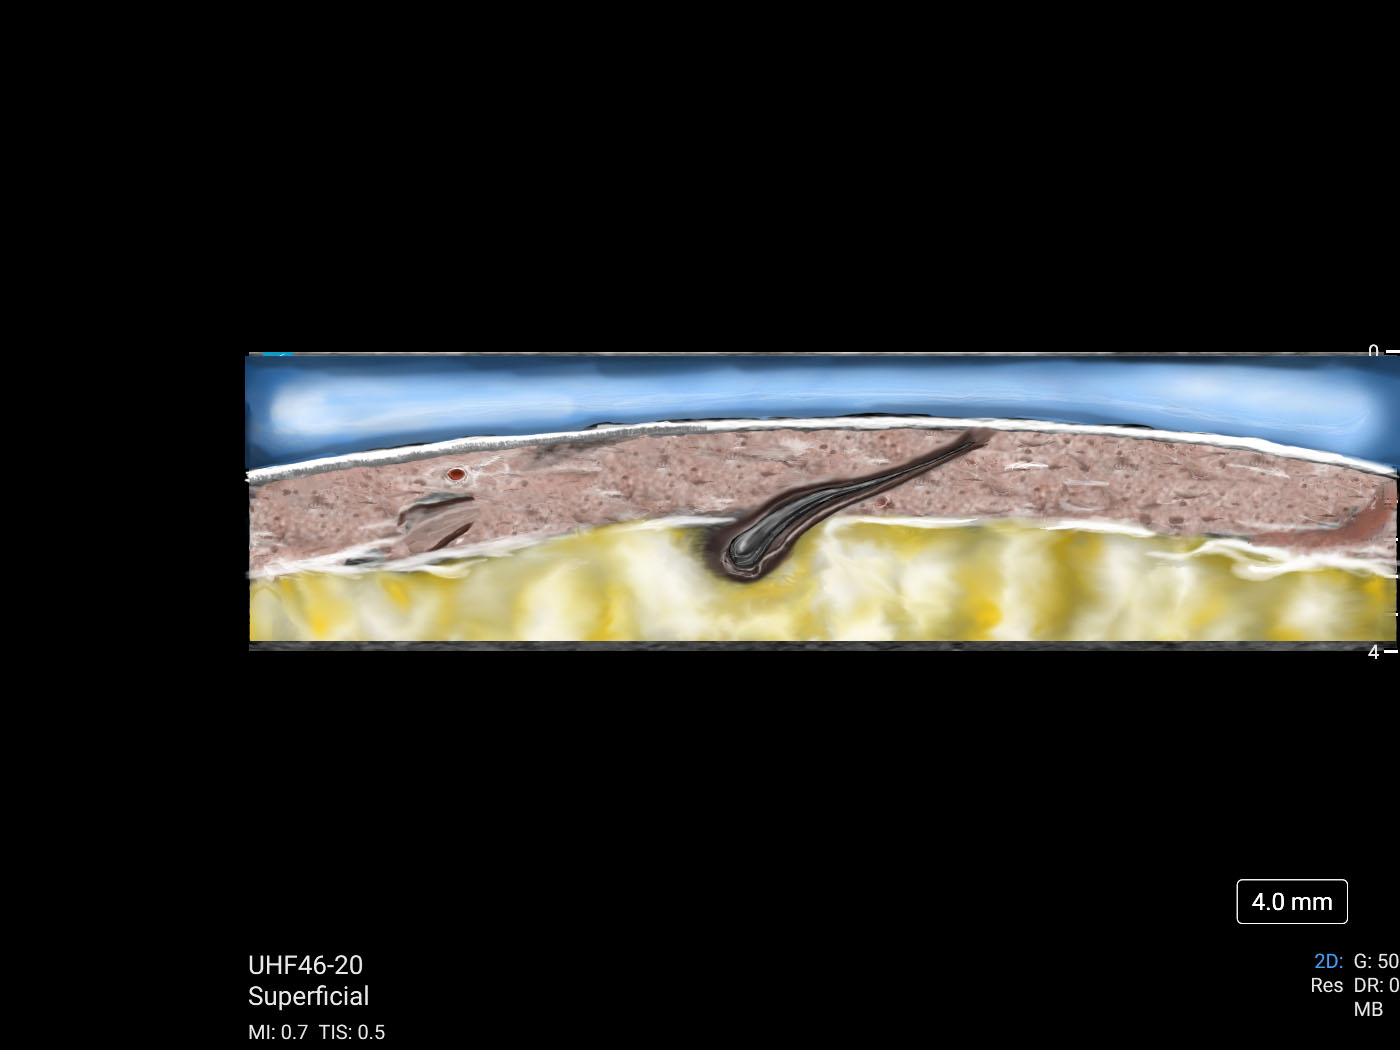

Bringing clinical scans to life

MSK Market Development Director, Daniel Shelton, shows off the capability of Sonosite UHF 46-20 with scans of a hair follicle and a vein. The scans were then illustrated to reveal details less obvious to the non-clinical eye. Image Image Hair follicle on the back of a child's calf  Image Image Vein (small superficial branch), the cephalic on the distal 1/3 forearm  …

Sonosite UHF 46-20 Featured in ICE Magazine

FUJIFILM Sonosite's UHF46-20 was recently featured in ICE magazine! With a minimum scan depth of 4mm, the UHF46-20 Transducer enables clinicians to clearly visualise the first one to two centimetres beneath the skin and identify structures smaller than 1mm.FUJIFILM Sonosite designs point-of-care ultrasound systems, ultrasound transducers, software, & ultrasound accessories with real-world customer needs in mind. Contact Us for more information.Read about the article here.Learn More